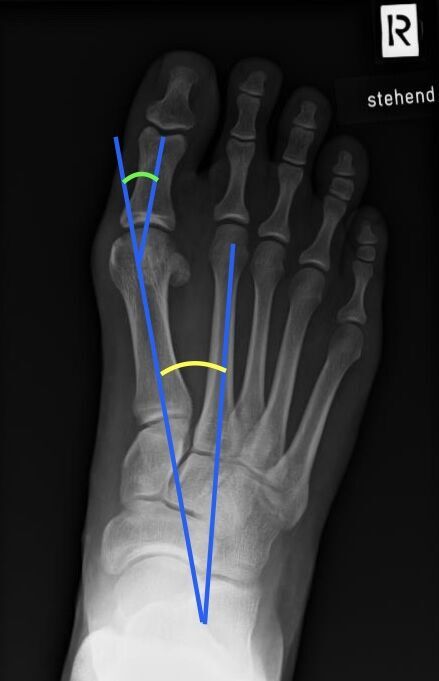

Ergänzend zur Untersuchung sollte ein Röntgenbild des ganzen Fußes unter Belastung in zwei Ebenen angefertigt werden. Spezielle Winkelmessungen ermöglichen die Bestimmung des Schweregrades der Fehlstellung. Zeichen des Gelenkverschleißes werden sichtbar und können bei der Erstellung des Therapiekonzeptes berücksichtigt werden.